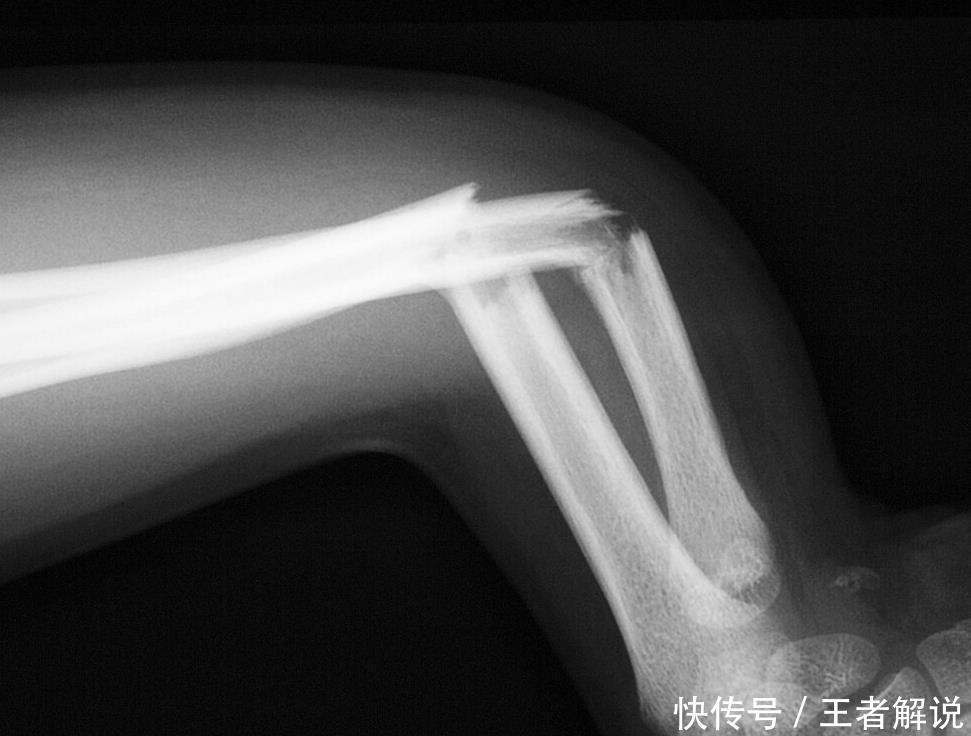

随着生活水平和物质条件的提升,越来越多的食物被搬上我们的餐桌,然而食物的搭配不合理却对身体健康造成较大危害。尤其是我们的骨骼非常容易引起损伤,错误的食物选择就容易导致骨质疏松的发生,而容易引起骨折,为生命安全埋下了较大隐患。

这段时间赵阿姨总感觉自己腰酸背痛,还以为是休息不好,就让儿媳妇请假两天好让自己休息一下,然而并没有什么用,腰疼得无法直立,无奈之下去了省里医院进行检查。医生听了赵阿姨的讲述之后,给她进行了骨密度检查,骨密度竟然低至-1.5,属于严重的骨质疏松,这和赵阿姨日常高盐饮食有着很大的关系。